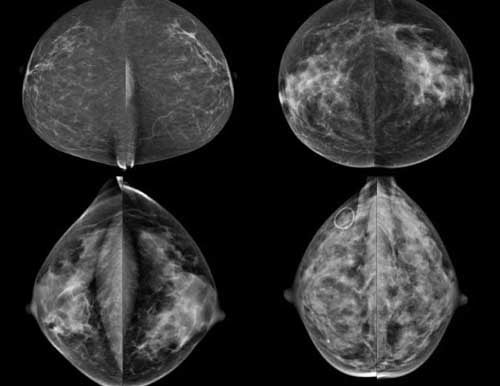

Recent studies have found that dense breast tissue is a strong independent risk factor for breast cancer. Breasts are composed of fat and fibroglandular tissue. Dense breast fibroglandular tissue appears white on a mammogram. Abnormalities and tumors also appear white on mammograms, causing them to be difficult to spot in dense breasts until the cancers are much larger and possibly in advanced stages.